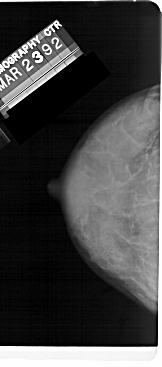

A_1482_1.RIGHT_MLO

RIGHT_MLO LINES 5116 PIXELS_PER_LINE 2086 BITS_PER_PIXEL 12 RESOLUTION 43.5 OVERLAY